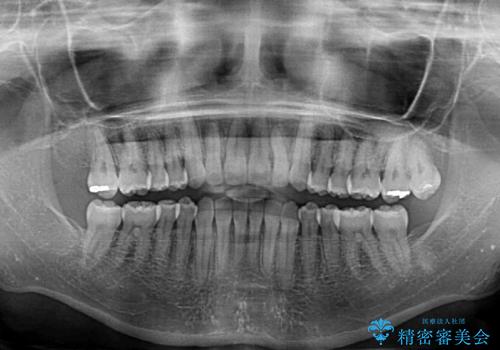

前歯の叢生と切端咬合 インビザラインによる矯正治療

- 前歯のデコボコを気にして来院された患者様です。

上下前歯の先端同士が接触する切端咬合であったため、上顎は歯列を拡大し、下顎はIPR(歯と歯の間を削る)により叢生を解消しながら歯列を小さくすることとしました。

治療前から歯肉退縮が認められ、矯正治療により悪化する可能性が考えられたため、無理のない歯の移動と頻繁な経過観察を行いました。

切端咬合はスムーズに解消され、前歯の負担を軽減させることができました。